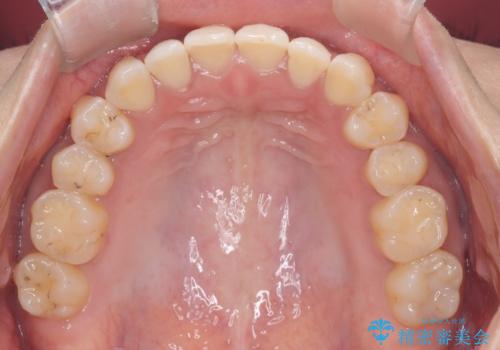

再矯正 前歯のガタツキをマウスピース矯正で治療したい

- 前に矯正治療をしたが、後戻りしてガタツキが出てきたので、治したいとのことで来院されました。

ワイヤー治療とマウスピース矯正、2通りの治療を提案させていただき、マウスピース矯正治療を希望されましたので、インビザラインによる治療を開始しました。